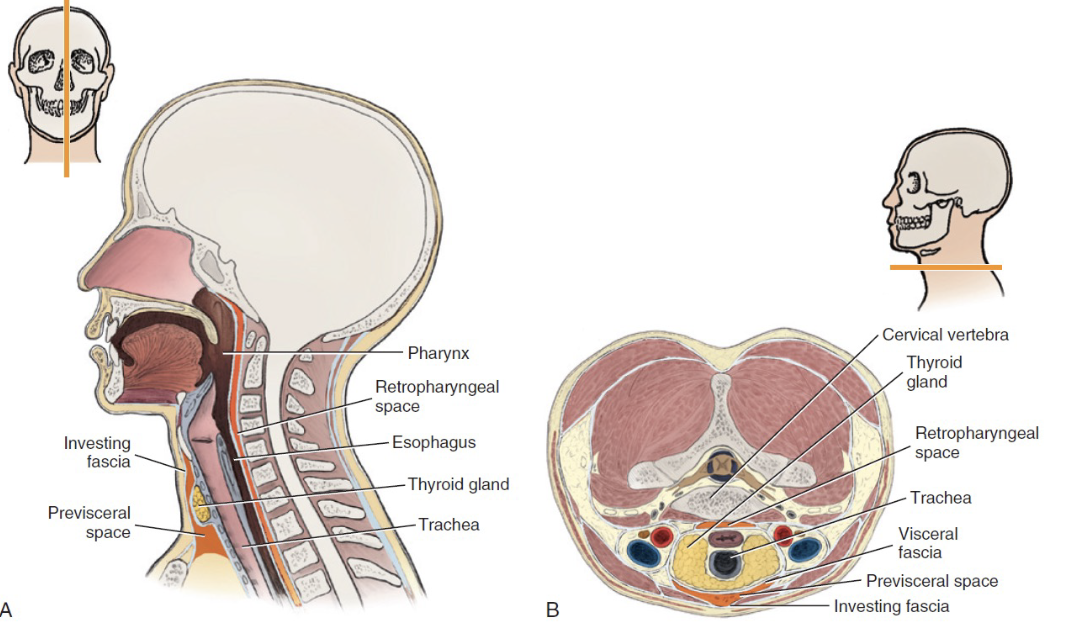

Neck

-

Investing fascia

- 最外層

-

Carotid fascia

-

Visceral fascia

- 食道呼吸道

-

Vertebral facial

Cervical spaces

Previsceral space

Parapharyngeal space

Retropharyngeal space

- Dangerous space

- Sup. pharyngeal constrictor m.後

Perivertebral & Paravertebral space